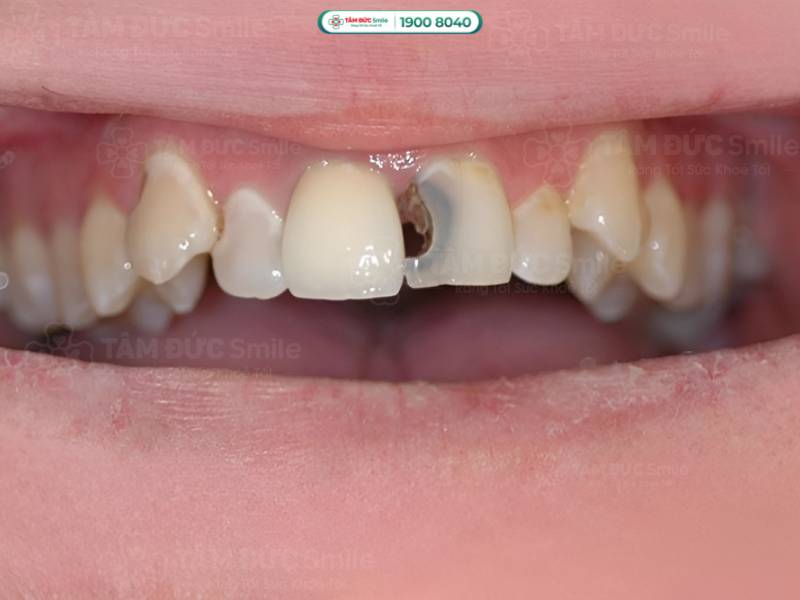

1.3.5. Sâu răng ảnh hưởng đến thẩm mỹ nụ cười

Sâu răng làm cho răng xỉn màu, tạo thành các lỗ sâu màu đen trên răng, rụng răng,... tất cả đều làm mất thẩm mỹ nụ cười. Nếu sâu răng xuất hiện ở răng cửa, nụ cười sẽ kém duyên hơn. Sâu răng làm bạn trở nên tự ti, ngại hé răng, ít cười khi giao tiếp với mọi người xung quanh. Sâu răng cản trở quá trình giao tiếp, từ đó dễ làm mất đi cơ hội thăng tiến trong công việc cũng như trong các mối quan hệ.

Sâu răng, đặc biệt là răng cửa sẽ làm mất thẩm mỹ nụ cười